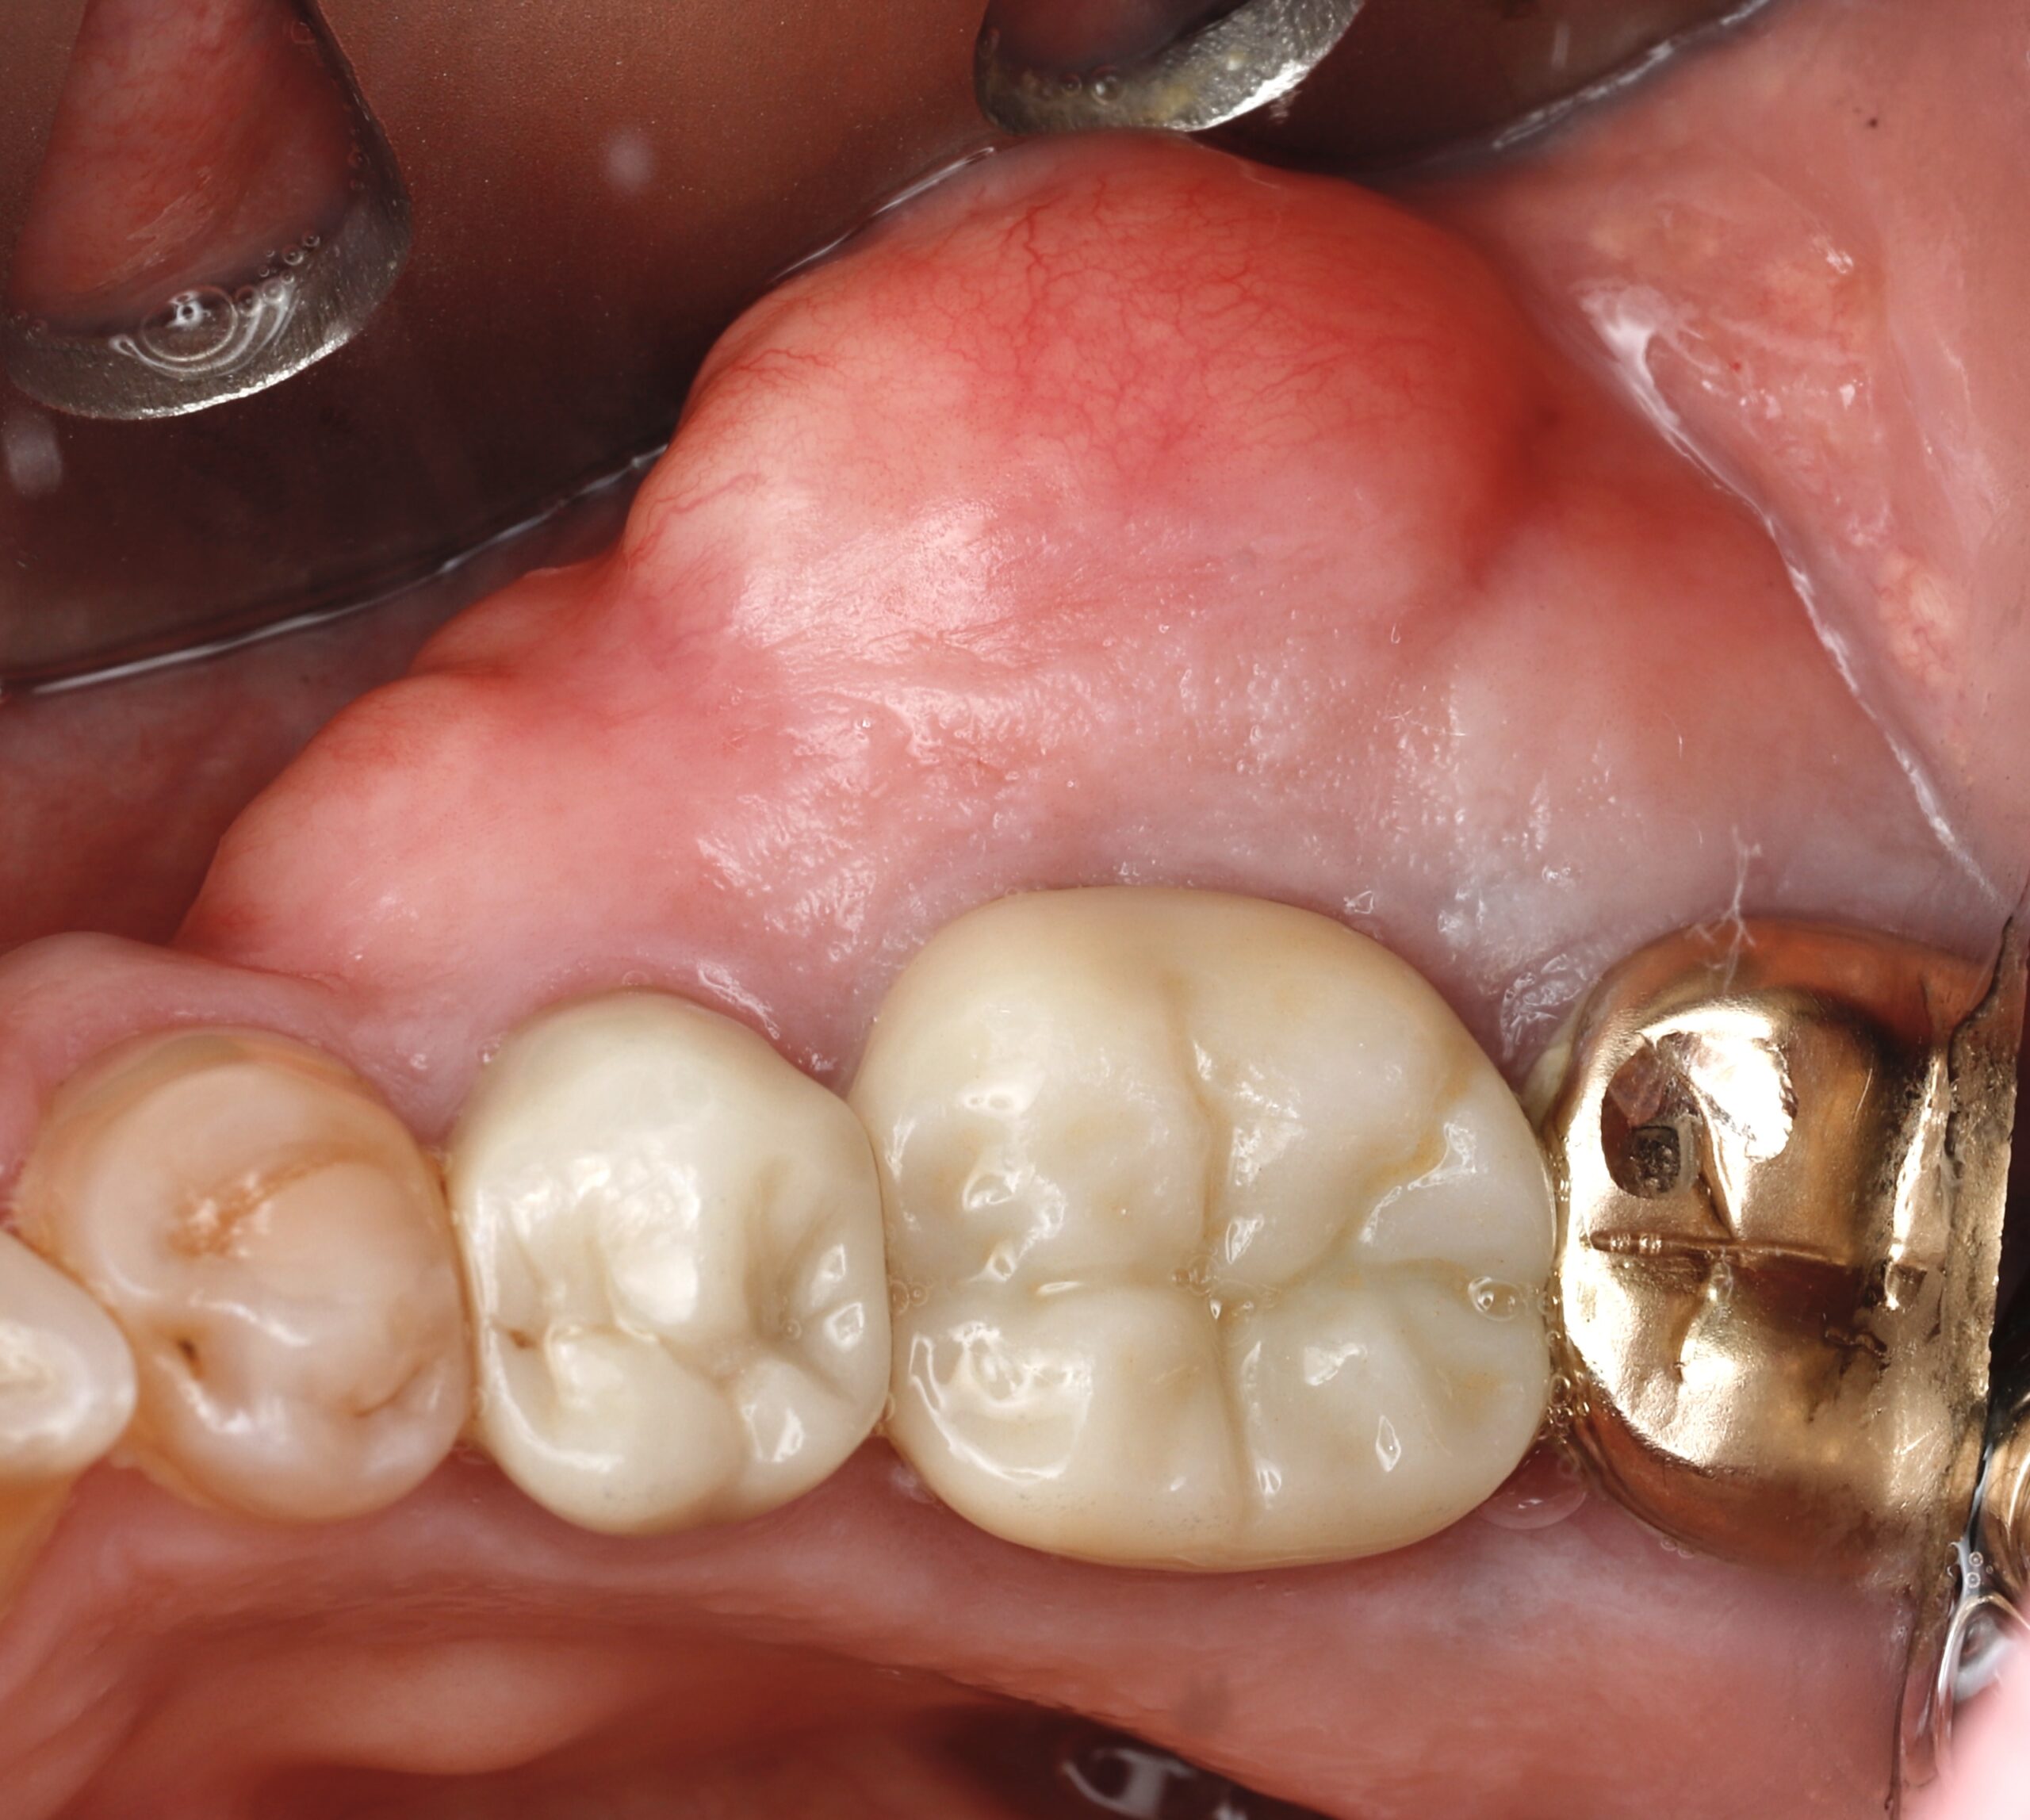

For most people, the inside of the mouth feels smooth and consistent. But some patients develop extra bony growths—called tori—along the roof of the mouth (palatal tori), the inside of the lower jaw (mandibular tori), or other areas. While tori aren’t dangerous, they can become a frustrating obstacle in daily life.

Patients often tell us they first notice tori when their dentist has trouble fitting a retainer, denture, or appliance. Others say the bumps cause irritation while eating or make speaking feel awkward. In some cases, the tori grow large enough to interfere with normal function altogether.

Tori are harmless, noncancerous bone growths that form in the mouth. They can vary in size, shape, and location. Some remain small and unnoticed for years, while others grow large enough to cause problems.